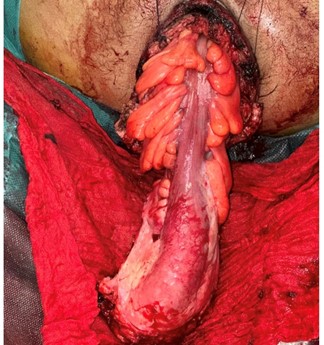

- Findings: Complete irreducible and necrotic rectosigmoid prolapse

Surgical steps:

- Circumferential incision 15 mm above the pectinate line

- Dissection and exteriorization of the entire prolapsed rectum and sigmoid

- Vascular control and resection of the diseased segment

- Myorrhaphy of the levator ani and sphincter repair with separate sutures

- Coloanal anastomosis using interrupted absorbable sutures

Figure 4: Intraoperative view of the prolapsed rectosigmoid exteriorized through the anal canal.